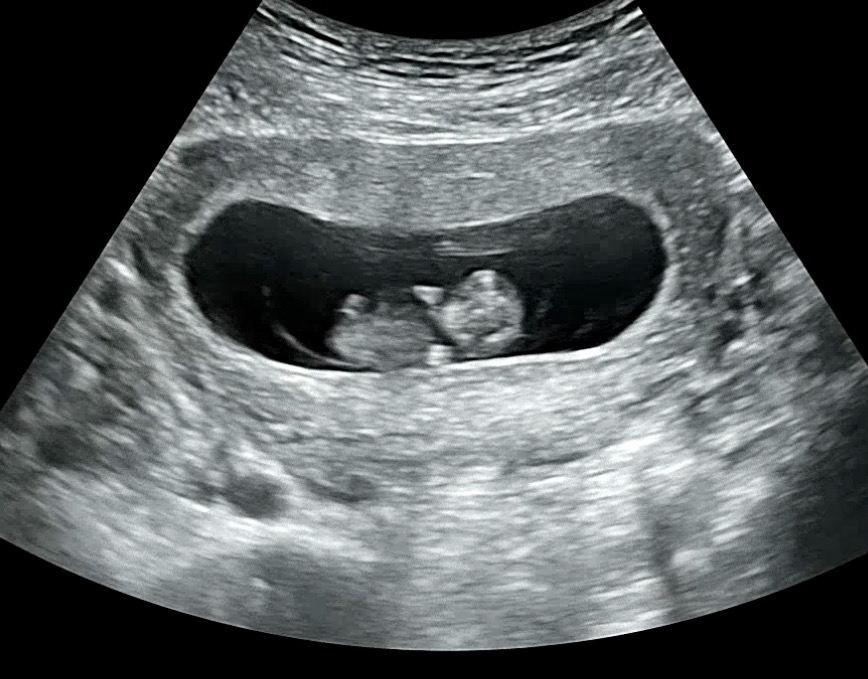

10주 0일차

8주 0일차에 젤리곰 못보고 10주쯤 되면 젤리곰이 아닐거같아서 속상했는데 저도 귀여운 젤리곰 보고왔어요🥹 보자마자 우와!귀여워! 해서 다들 웃었네요 ㅋㅋㅋㅋ 몸무게가 자꾸 늘어서 고민이었는데 그만큼 잘크고있는것 같아서 기분좋아요 ㅎㅎ